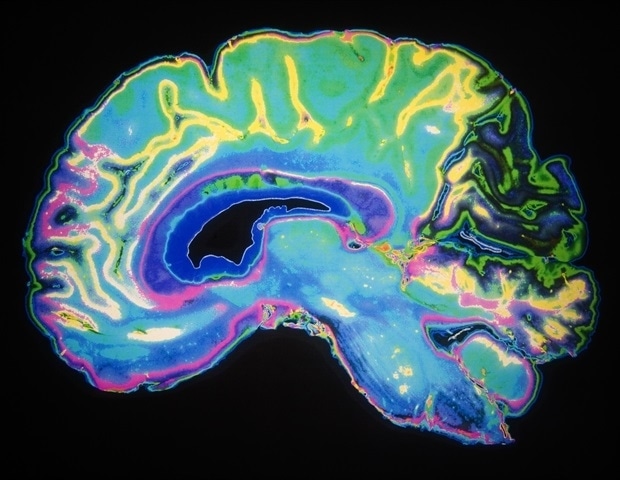

Хотя таргетное облучение может быть эффективным методом лечения опухолей головного мозга, последующий потенциальный некроз обработанных участков может быть трудно отличить от опухолей на стандартной МРТ. Новое исследование, опубликованное сегодня под руководством профессора Йоркского университета в Инженерной школе Лассонд, показало, что новый метод на основе искусственного интеллекта позволяет лучше различать два типа поражений на расширенной МРТ, чем только человеческий глаз. Это открытие может помочь врачам более точно выявлять и лечить проблемы.

Исследование впервые показывает, что новые методы искусственного интеллекта, управляемые вниманием, в сочетании с усовершенствованной МРТ могут с высокой точностью различать прогрессирование опухоли и радиационный некроз у пациентов с метастазами в головной мозг, прошедших лечение. при стереотаксической радиохирургии. Своевременная дифференциация между прогрессированием опухоли и радиационным некрозом после лучевой терапии опухолей головного мозга является важнейшей проблемой в онкологических центрах, поскольку эти два состояния требуют совершенно разных подходов к лечению».

Садеги-Наини и его коллеги представили трехмерную модель искусственного интеллекта с глубоким обучением с двумя усовершенствованными механизмами внимания для дифференциации прогрессирования опухоли и радиационного некроза с использованием специализированного метода МРТ, называемого переносом насыщения химического обмена (CEST), и обнаружили, что ИИ способен различать между прогрессированием опухоли и радиационным некрозом. два состояния с точностью более 85. Садеги-Наини говорит, что с помощью стандартной МРТ эти два состояния точно диагностируются примерно в 60 процентах случаев, а при использовании только более продвинутых методов МРТ этот показатель увеличивается примерно до 70 процентов.